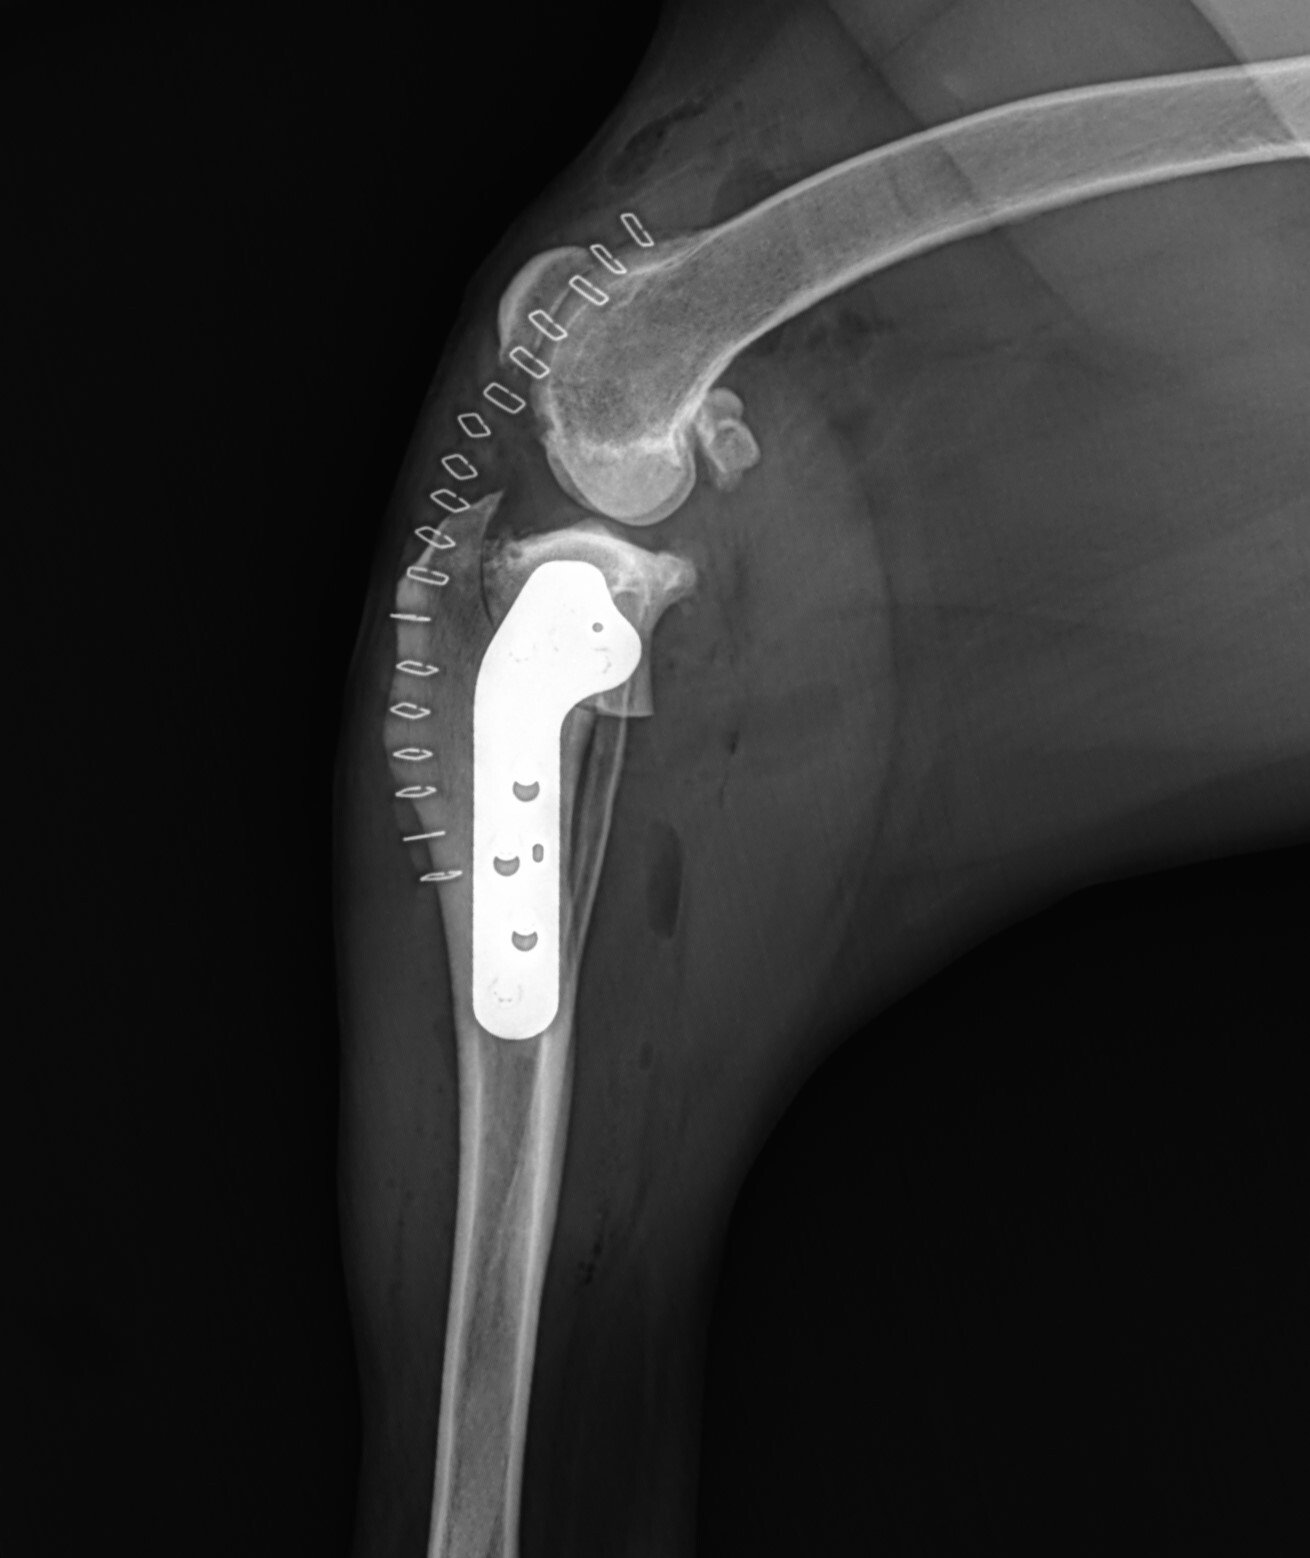

from tplocharlotte.com

TPLO Surgery Dogwood Veterinary Surgical Care Charlotte, NC